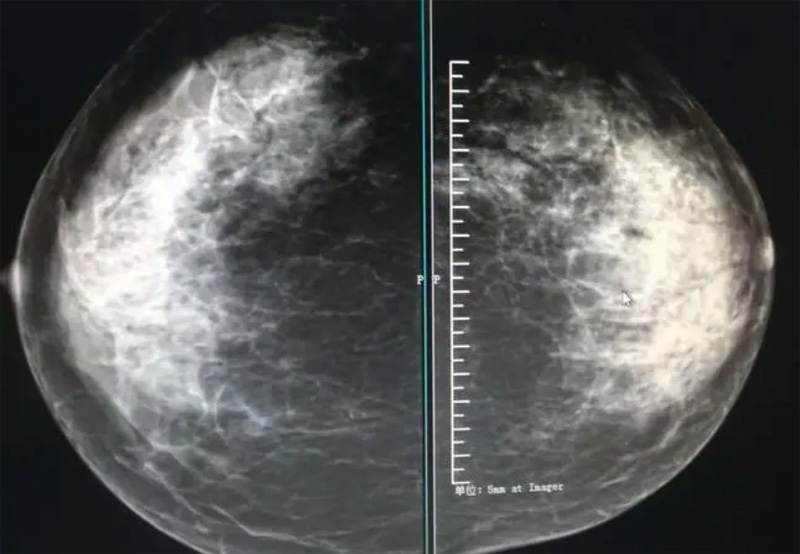

乳腺DR摄影体位有头尾位及内外侧斜位,乳房在片子的中央,乳头切线位,可见小部分胸大肌,内侧乳腺组织应全部包括在片中,外侧乳腺组织尽可能包括在片中。一张好的MLO位图像显示如下:乳房被推向前上,乳腺实质充分展开,胸大肌可见,较松弛,下缘达到乳头水平,乳头在切线位,部分腹壁包括在片中,但与下部乳腺分开,绝大部分乳腺实质显示在片中。乳腺组织外缘可见乳头的轮廓;乳腺后方的脂肪组织被很好地显示出来,乳房无皱褶。对于CC位及MLO位显示不良或未包全的乳腺实质,可以根据病灶位置的不同选择以下体位:外内侧位(LM)、内外侧位(ML)、内侧头尾轴位(MCC)、外侧头尾轴位(LCC),尾叶位(CLEO)及乳沟位。在临床实践中,对于常规体位上发现的异常改变,可以进一步采取一些特殊的摄影技术,包括局部加压摄影、放大摄影或局部加压放大摄影技术。

2、规范观图程序:屏幕软阅读或在专用日光观片灯下胶片阅读,后者应同时准备白炽强光灯及观片放大镜。注意双侧乳腺配对观察,推荐双眼横向扫描,进行双乳相同部位图像比较分析。

3、乳腺实质背景的确定:观察乳腺实质与脂肪的构成比例,了解乳腺实质类型,以判断对某些乳腺摄影征象敏感性的影响,有利于确定乳腺摄影对疾病的诊断价值。

必须指出的是,美国放射学会提出的乳腺影像报告和数据系统(Breast Imaging Reporting and Data System, BI-RADS)将乳腺分为4型:脂肪型(乳腺内几乎全部为脂肪组织,腺体组织占25%以下)、少量腺体型(乳腺内散在腺体组织,大约占25%~50%)、多量腺体型(乳腺呈不均匀致密表现,腺体组织大约占51%~75%)、致密型(乳腺组织非常致密,腺体组织占75%以上)。这种分型的主要意义在于说明X线对不同乳腺类型中病变检出的敏感性不同,对发生在脂肪型乳腺中病变的检出率很高,而对发生在致密型乳腺中病变的检出率则有所降低,临床医师了解这一点很重要。